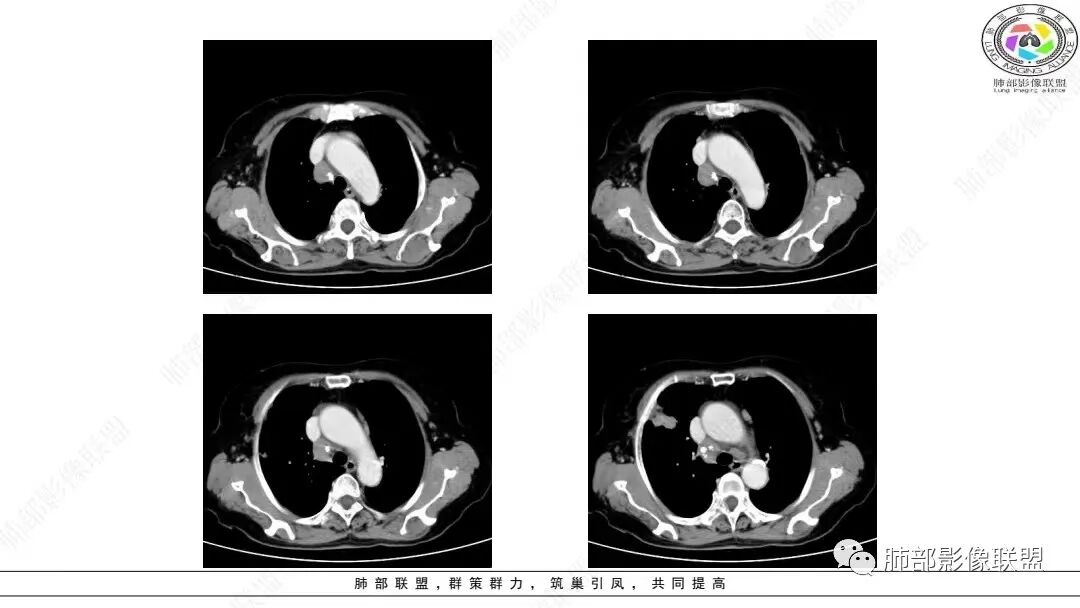

2.影像学特点:右肺上叶前段胸膜下不规则较大团块影,边界清楚欠光整,浅分叶,肺血管支气管出入,边缘膨隆胸膜凹陷具有一定张力,未见典型粗短毛刺,部分围以边界清楚的磨玻璃影,灶周小叶间隔增厚。块影密度不均,渐进性强化,可见砂砾样钙化,未见明显液化坏死或空洞。增强后病灶显示渐进性强化。MIP显示病灶内肺动脉穿行、并部分肺动脉受侵变细。纵隔及右锁骨上(胸廓入口)见肿大淋巴结。两肺可见多发大小不一的结节影,边界清楚,随机分布。

胸椎体溶骨性吸收破坏,突破骨皮质。腹部扫描未见肿块影。